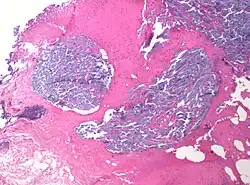

Desmoplastic small round cell tumour, with desmoplasia surrounding nests of cancer cells.

In medicine, desmoplasia is the growth of fibrous connective tissue.[1] It is also called a desmoplastic reaction to emphasize that it is secondary to an insult. Desmoplasia may occur around a neoplasm, causing dense fibrosis around the tumor,[1] or scar tissue (adhesions) within the abdomen after abdominal surgery.[1]

Desmoplasia is usually only associated with malignant neoplasms, which can evoke a fibrotic response invading healthy tissue. Invasive ductal carcinomas of the breast often have a stellate appearance caused by desmoplastic formations.